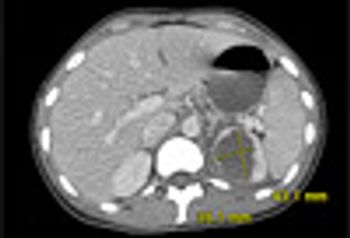

Renal Abscess Caused by Klebsiella PneumoniaePublished: February 28th 2012 | Updated: